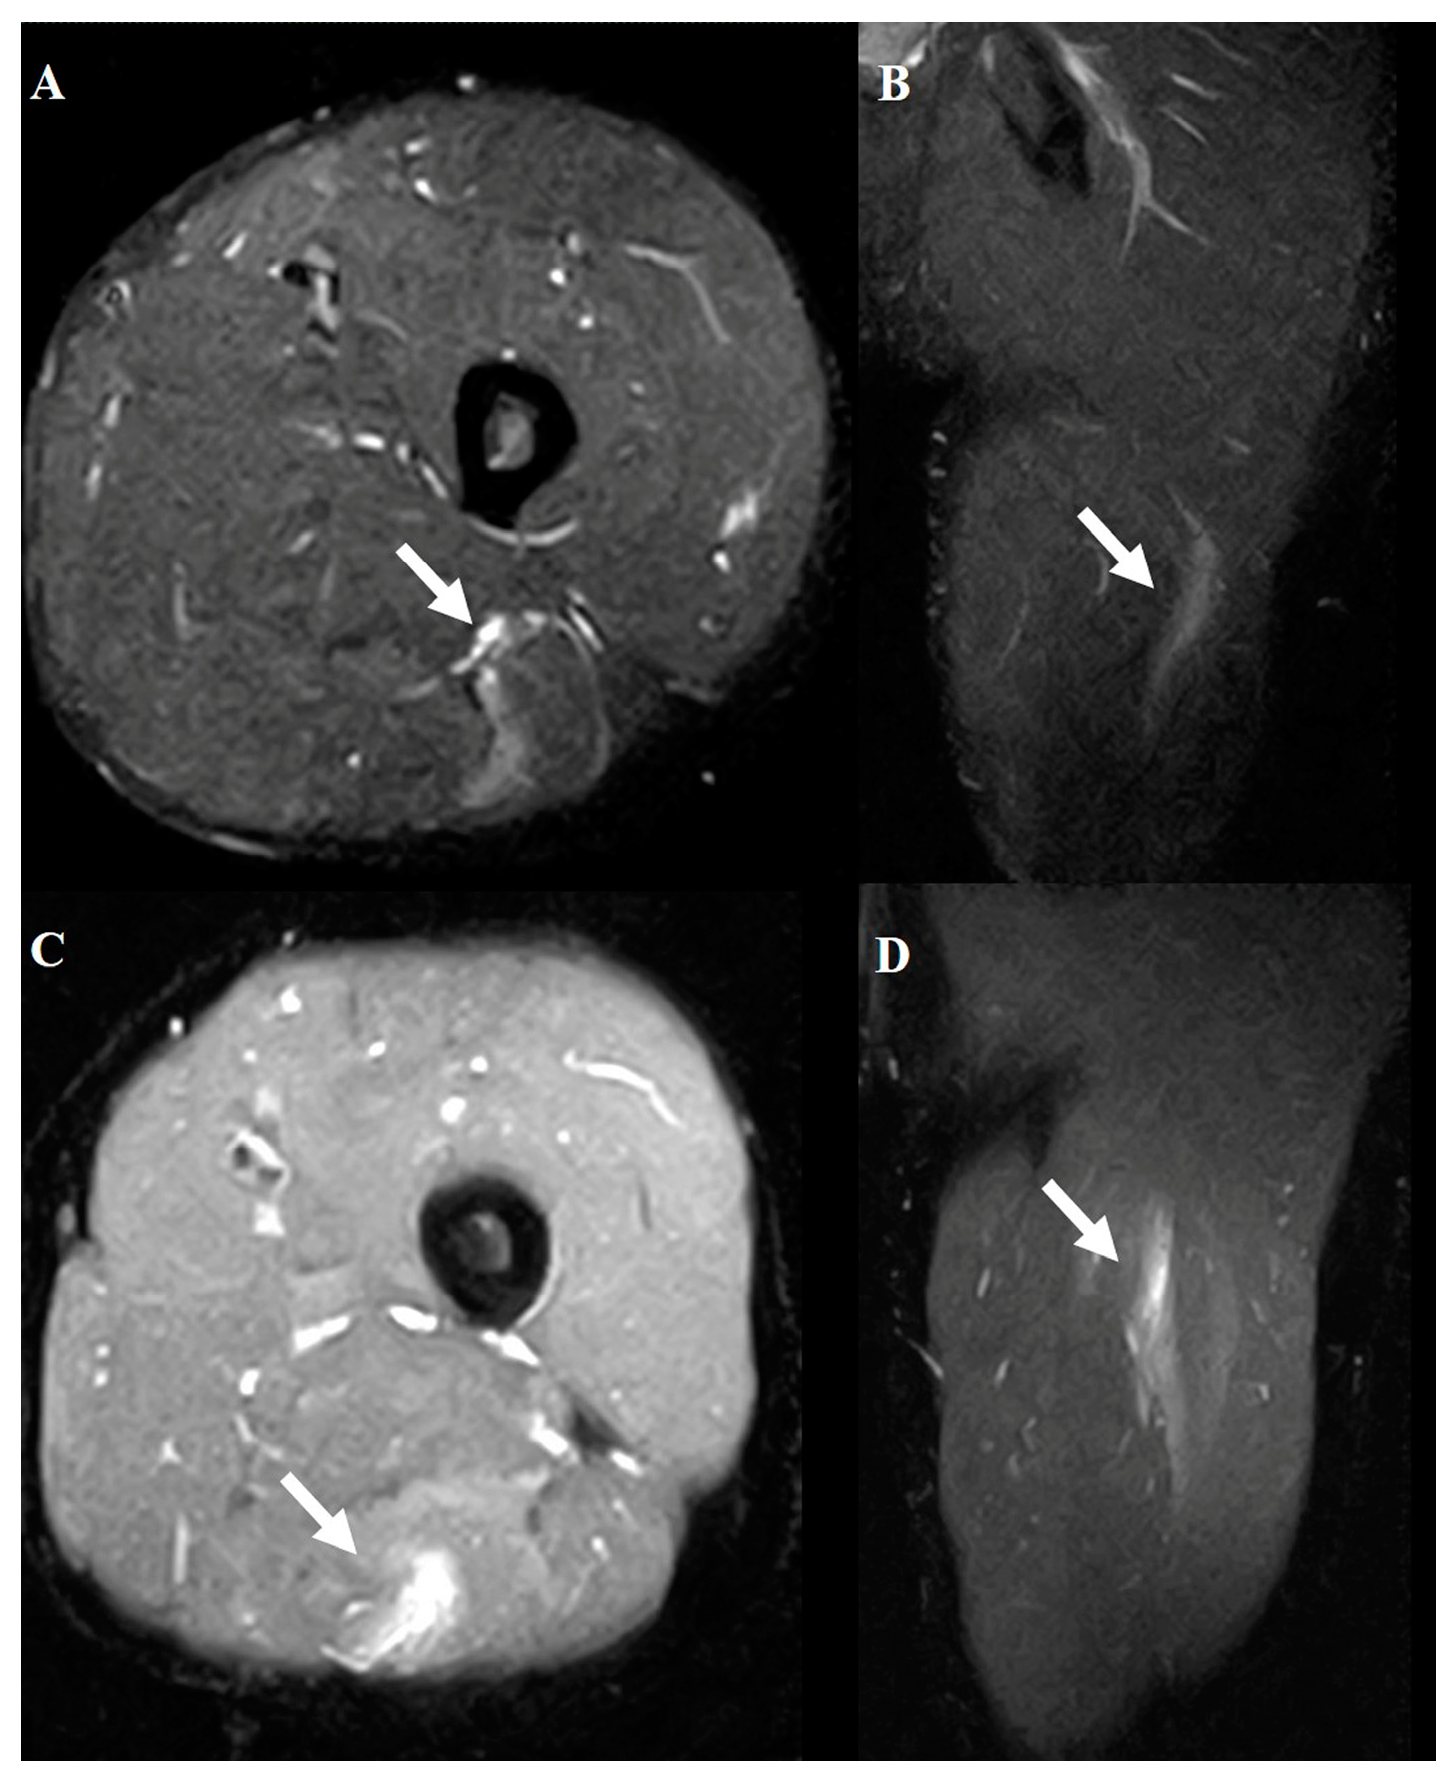

2.4. Hamstring Muscle Diagnosis Using MRI